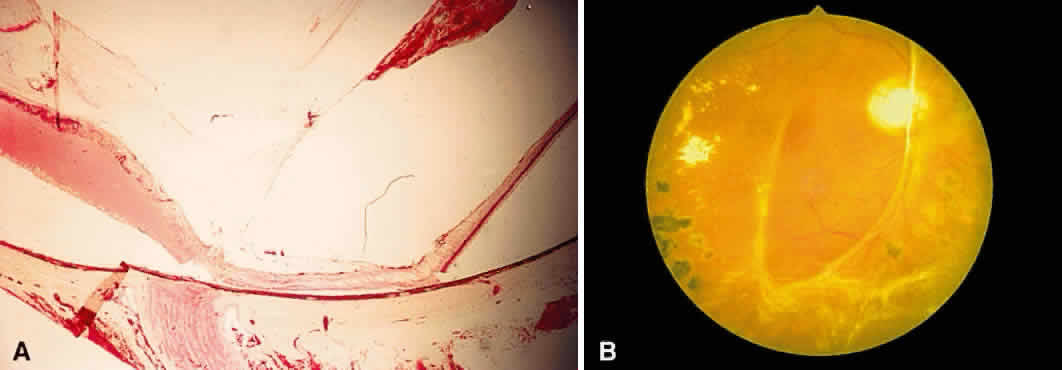

the internal limiting membrane (see Fig. 11B). A hemorrhage located between the retinal pigment epithelium and Bruch's

membrane also spreads in a plane parallel to the orientation

of the membrane (Fig. 12). However, its extent is limited by the adhesion of the pigment epithelium

to Bruch's membrane, in contrast to a nerve fiber layer hemorrhage, where

|

Fig. 12. Section of the eye showing subretinal hemorrhage. (Courtesy of Ralph C. Eagle Jr, MD, Philadelphia, PA) Fig. 12. Section of the eye showing subretinal hemorrhage. (Courtesy of Ralph C. Eagle Jr, MD, Philadelphia, PA)

Fig. 17. A. A histologic section stained with H & E demonstrating vascularized

membranes on the disc and retina. Tractional retinal detachment is present. Notice

the subretinal fluid (amorphous eosinophilic material). B. Fundus photograph of fibrous tissue emanating from the disc in patient

with proliferative diabetic retinopathy. The disc is pale; the macula

is edematous with exudate. Pigmented laser spots are visible temporally. Fig. 17. A. A histologic section stained with H & E demonstrating vascularized

membranes on the disc and retina. Tractional retinal detachment is present. Notice

the subretinal fluid (amorphous eosinophilic material). B. Fundus photograph of fibrous tissue emanating from the disc in patient

with proliferative diabetic retinopathy. The disc is pale; the macula

is edematous with exudate. Pigmented laser spots are visible temporally.